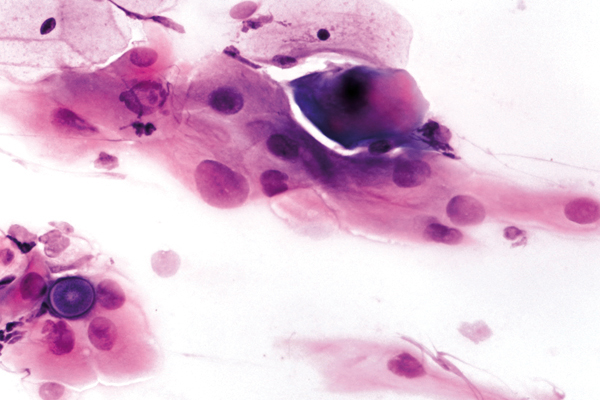

Februar

richtige Antwort:

d. Histiozytäre Riesenzelle

- man findet sie häufig bei Entzündungen und nach operativen Eingriffen

- polymorphes Erscheinungsbild mit häufig vakuolisiertem Zytoplasma

- gleichmäßige Form und Größe der Zellkerne